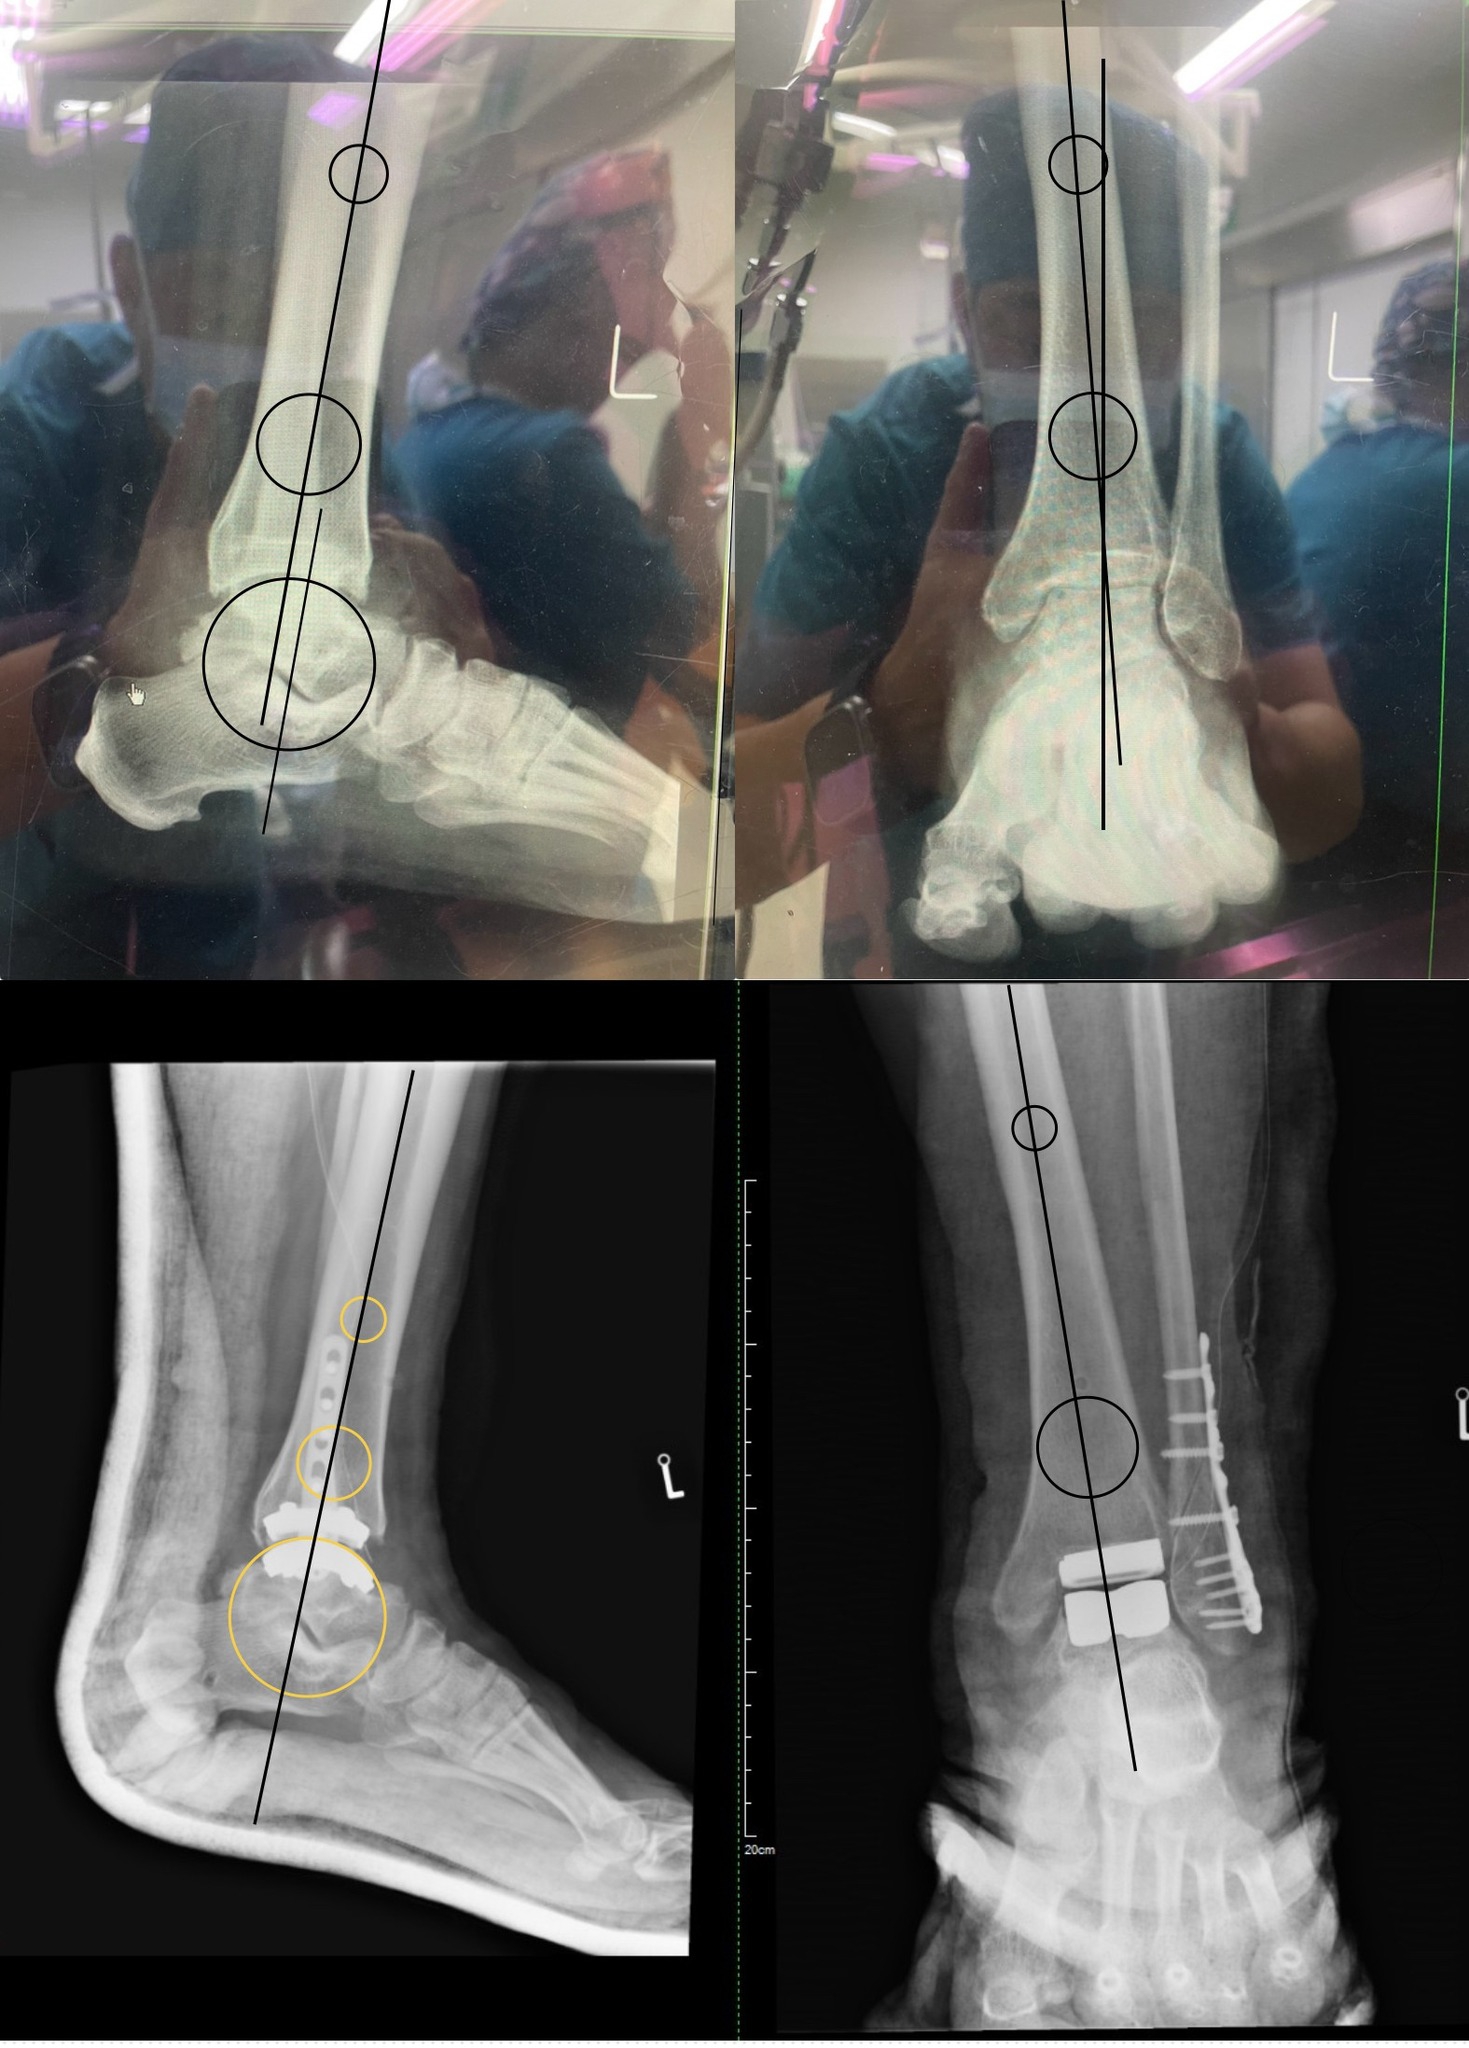

今天在團隊的協助下,順利完成一例 捷邁(Zimmer Biomet)人工全踝關節置換手術。

透過精準的術前規劃與骨切導引,結合捷邁系統的高穩定性設計,

手術團隊能更精準地重建踝關節的力線與活動軸心,